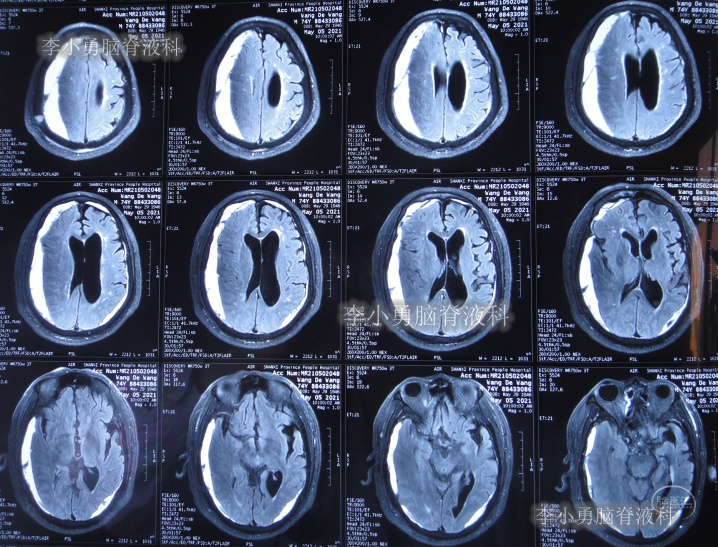

2021年5月5日(腰大池腹腔分流术后38天,即拔除硬膜下血肿引流管16天),查头部核磁和腰椎核磁(图-10、图-11)后认为可能是颅内感染或和堵管。

图-10:2021年5月5日头部核磁

图-11:2021年5月5日腰椎核磁